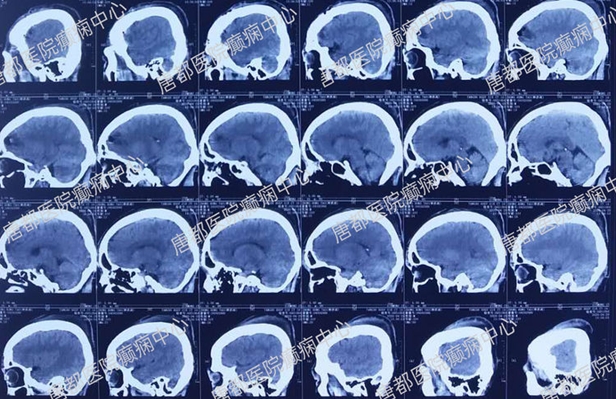

术后CT检查: